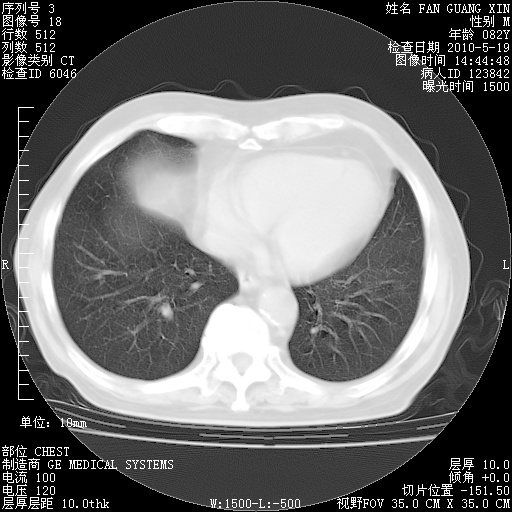

复查肺部CT,明显好转。为什么发热呢?

治疗3周后的肺部CT